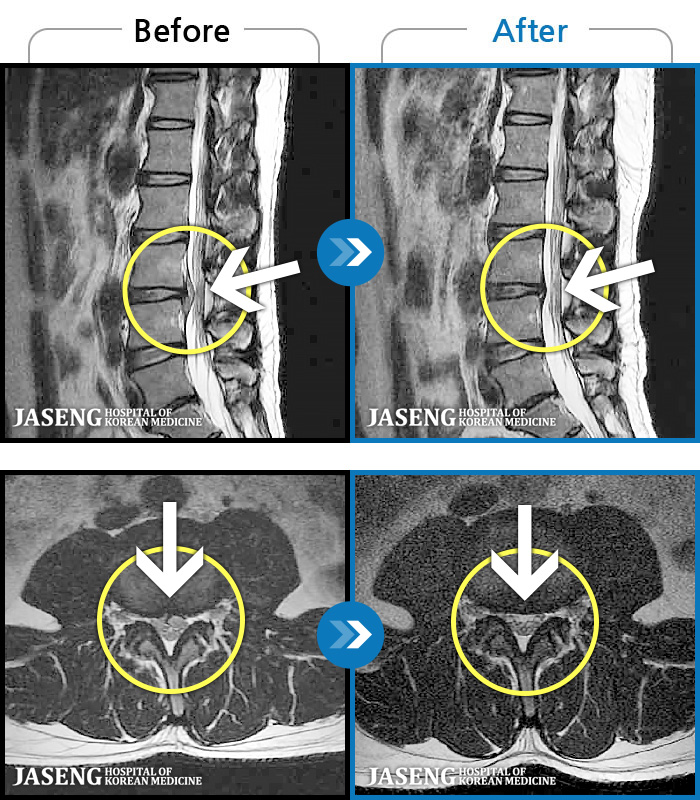

MRI ġ

119 MRI ũ ʸ Ȯϼ.

[Կñ:24.06.08~24.08.31]

[_㸮ũ] ġ ٸ ſ ؿ.

No.117

ȸ 554

2024.12.24